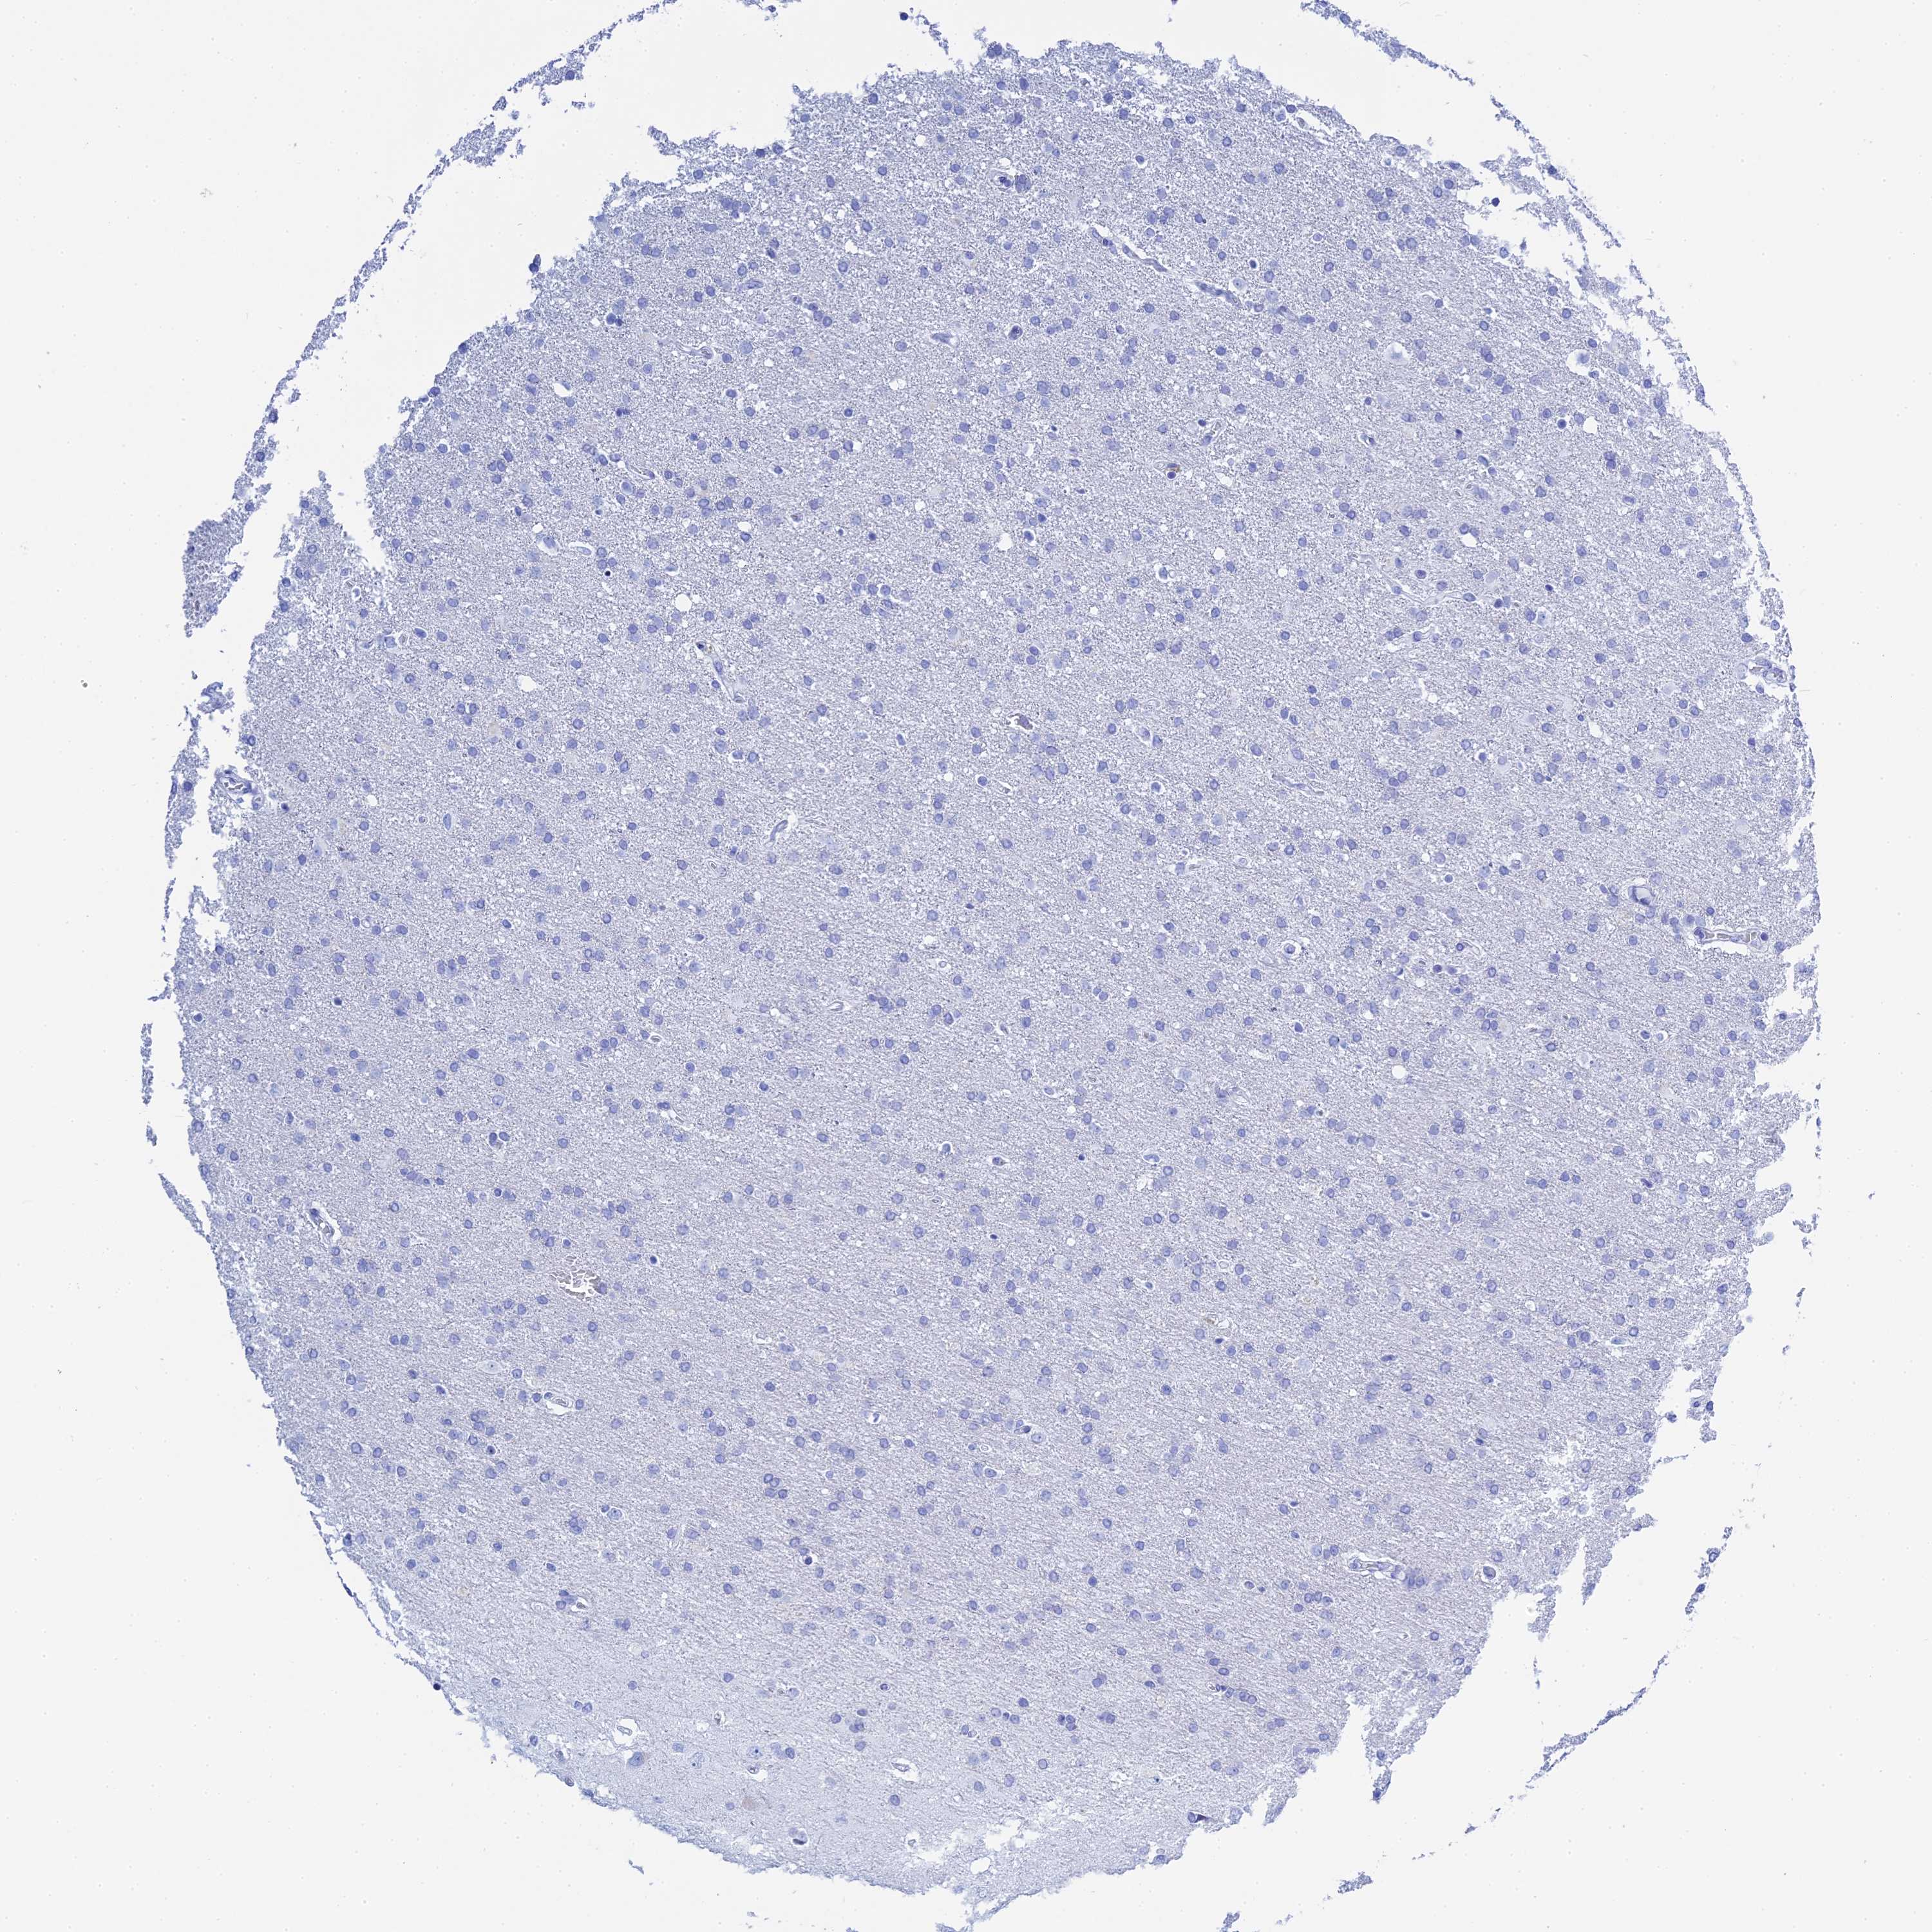

GLIOMA - Protein expressioni

A mouse-over function shows sample information and annotation data. Click on an image to view it in a full screen mode. Samples can be filtered based on level of antibody staining by selecting one or several of the following categories: high, medium, low and not detected. The assay and annotation is described here.

Note that samples used for immunohistochemistry by the Human Protein Atlas do not correspond to samples in the TCGA dataset.

Antibody stainingi

Antibody staining in the annotated cell types in the current human tissue is reported as not detected, low, medium, or high, based on conventional immunohistochemistry profiling in selected tissues. This score is based on the combination of the staining intensity and fraction of stained cells.

Each image is clickable and will lead to virtual microscopy that enables deeper exploration of all samples and also displays staining intensity scores, fraction scores and subcellular localization as well as patient and tissue information for each sample.

Antibody HPA041915

Antibody HPA042513

Glioma, malignant, High grade

Glioma, malignant, Low grade